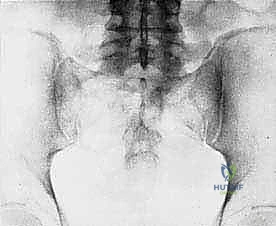

- Plain Radiography (FIG 2): While of limited value for early lesions, it provides an initial overview. As you can see in Figure 2A, we have a large lytic lesion of the right periacetabular region. Figure 2C shows a cartilage-forming lesion in the left ilium. However, plain films often underestimate the true extent of these tumors.

* CT with Intravenous Contrast and 3D Reconstruction (FIG 3): This is our workhorse for assessing bone involvement, destruction, and the critical relationship between the tumor and major pelvic blood vessels. It reveals any distortion of the pelvic anatomy and guides resectability. Figure 3A clearly shows extensive bone destruction and tumor extension into the pelvis and gluteal region. Figure 3C highlights an extensive tumor on the medial aspect of the ilium with destruction of the inner table.